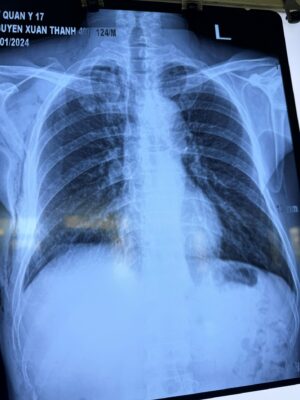

Bệnh nhân Nguyễn Xuân Th., 49 tuổi, tiền sử hút thuốc nhiều năm nay, không ghi nhận tình trạng bệnh lý mạn tính của phổi trước đây, vào khoa Ngoại chung, Bệnh viện Quân y 17 điều trị vì đau ngực phải đột ngột, khó thở nhiều, cảm giác tức nặng ngực phải, ho khan. Sau khi thăm khám lâm sàng, chụp Xquang ngực thẳng, bệnh nhân được chẩn đoán: Tràn khí màng phổi tự phát nguyên phát bên phải mức độ nặng theo dõi do vỡ kén khí phổi phải.

Hình ảnh X Quang ngực của bệnh nhân lúc nhập viện